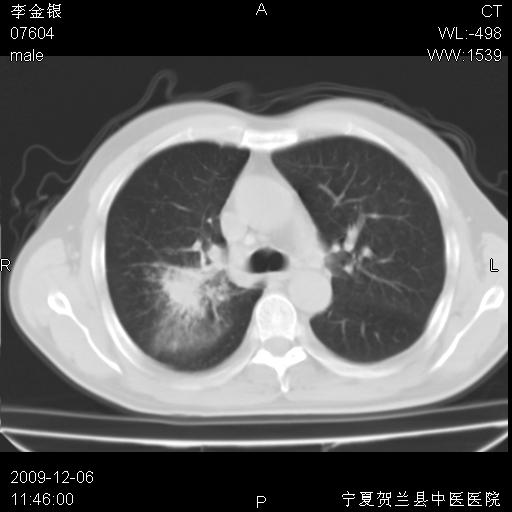

该病人 ,男,62岁,主因咳痰带血两天

考虑右肺中央型占位性病变并阻塞性肺炎.(右肺上叶支气管变窄),建议支纤镜检查.

支持右侧中央型肺癌伴上叶阻塞性炎症.

考虑右肺中心型肺癌伴阻塞性肺炎及右肺门淋巴结转移,建议纤维支气管镜进一步检查。

支气管壁明显增厚 管腔狭窄,腔静脉后多个淋巴肿大,结合年龄病史考虑右肺上叶中央型肺癌并阻塞性肺炎

右肺上叶后段支气管阻塞,右上肺门占位,相应肺段阻塞性肺炎,右肺门有淋巴结肿大。诊断右肺上叶中心型肺癌,阻塞性肺肺炎、右肺门淋巴结转移。

右上叶支气管狭窄,管壁增厚,远端斑片状软组织影,病灶邻近叶间裂,叶间裂无移位。

诊断右肺中央型肺癌。

那个片影应该大部分都是病灶,病灶沿肺段支气管分支生长,后段完全显示不清、闭塞。若为不张应该伴有叶裂的移位,若为炎症应有空气支气管征。